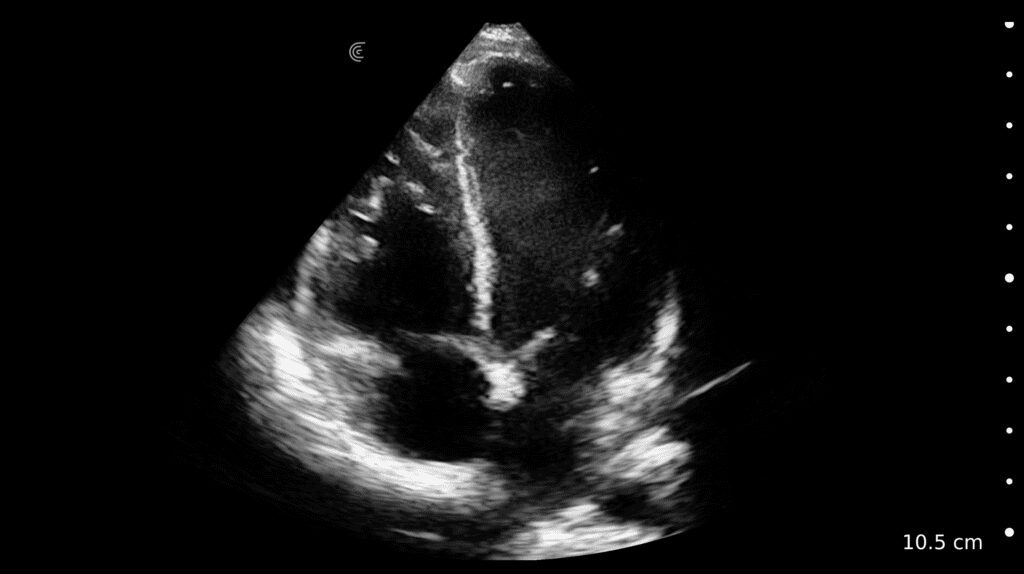

Color/Power Doppler Farb-/Powerdoppler Doppler couleur/puissant Doppler de color/potencia | |

Vascular